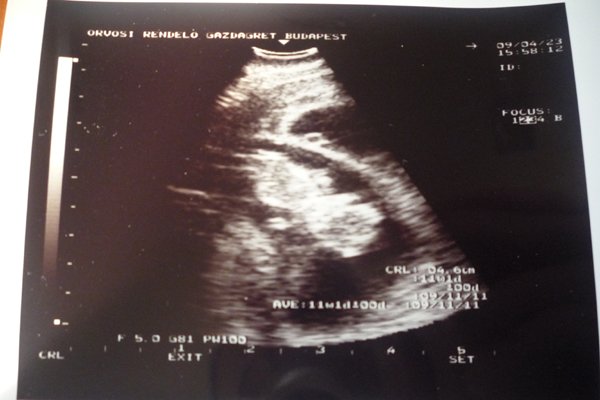

Dita: bocsi, de elfelejtettem leírni, hogy mekkorák. Tegnap voltak 4,6 cm-esek, mindketten!!! Egyénként a képeken lehet látni a méretüket is a CRL felirat mögött kivehető. :) És igen, őrület, hogy már ilyenkor megvan mindenük!!!! :D :D